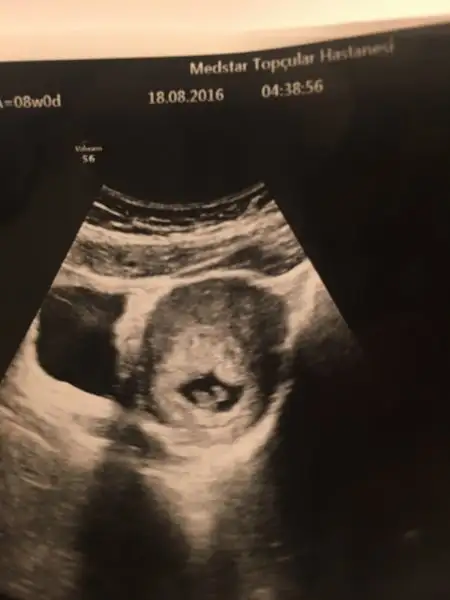

Arkadaslar merhaba yorumlar misiniz karindan 8 haftalik benim cinsiyet belli bakalim bu teori ben de tutacak mi

Eklentiler

• 20160910_110546.webp

10,2 KB · Görüntüleme: 189

• 20160910_110808.webp

9,2 KB · Görüntüleme: 193